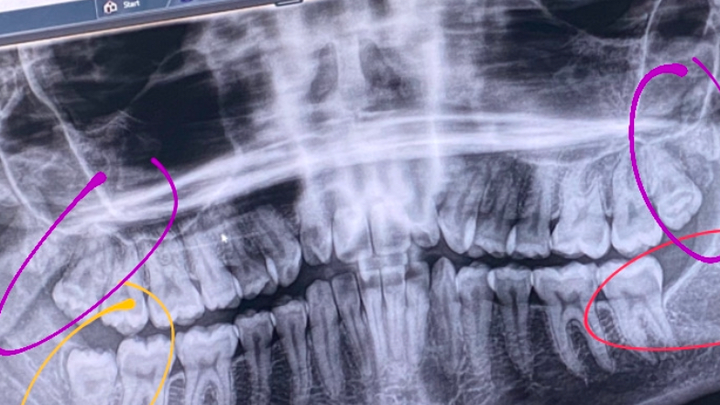

On Friday in the midst of the snowstorm I broke a tooth. Upon getting my examination on Monday I found out that I am going to need a root canal on my back left molar, and a cap on the tooth in front of it. In addition to this, it was revealed via x ray that my three remaining wisdom teeth are impacted, with the upper teeth having their roots embedded in my sinus cavity. I need to have these removed immediately, as they pose a significant risk to my overall health if they become infected or need a root canal. The initial amount I was quoted for these procedures was $7700. I am trying to raise part of this amount as I absolutely cannot afford this at all. Having an active infection is directly impacting my blood sugar and making my type 1 diabetes significantly harder to manage, so getting this taken care of as soon as possible is my top priority. Thank you for anything and everything you can give.